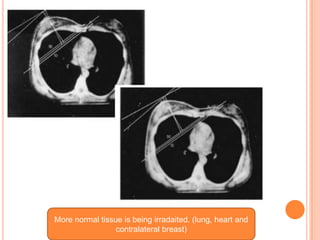

More normal tissue is being irradaited. (lung, heart and

contralateral breast)

Anterior field Oblique field

More normal tissueis being irradaited. (lung, heart and contralateral breast)